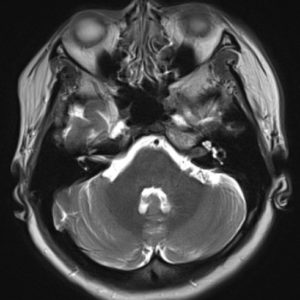

U dây VIII

Lượt xem: 140» 24-11-2018 -

U dây VIII

Lượt xem: 131» 24-11-2018 -

U dây VIII

Lượt xem: 143» 24-11-2018 -

U dây VIII

Lượt xem: 155» 24-11-2018 -

U dây VIII

Lượt xem: 124» 19-11-2018 -

U dây VIII

Lượt xem: 159» 05-11-2018 -

U dây VIII

Lượt xem: 239» 30-10-2018 -